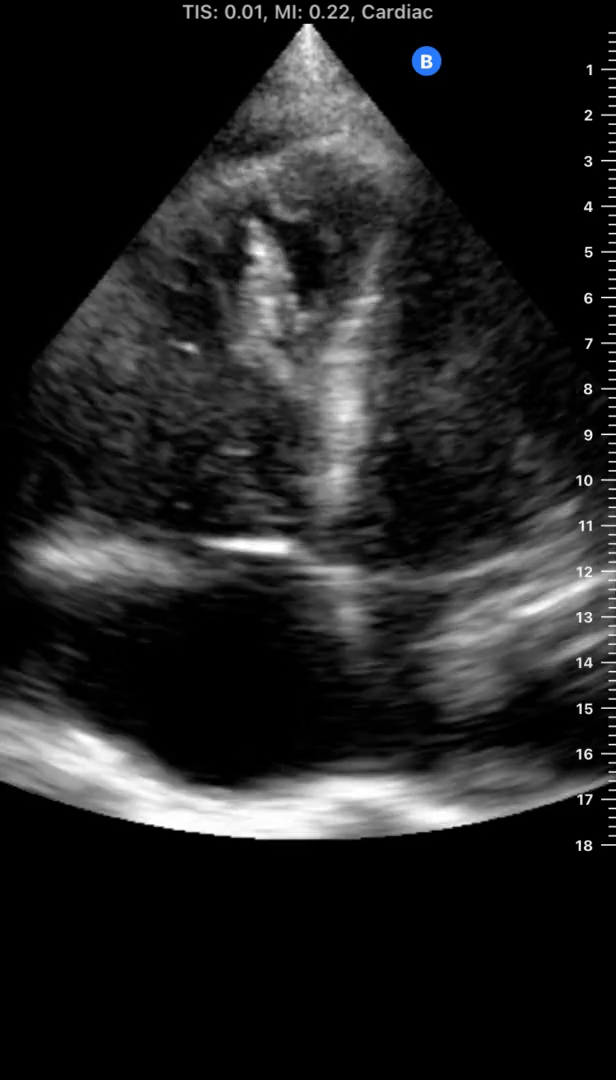

The name of this sign

12

1 pts

The location of abnormal fluid